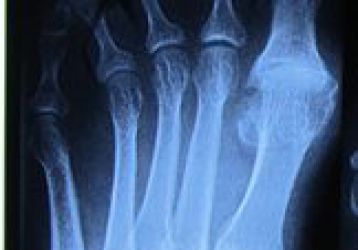

Лечение артроза стопы в домашних условиях: медикаменты, ЛФК, народная медицина

Лечение артроза суставов стопы в домашних условиях без докторов. Гимнастика, медикаменты, физиотерапия и народные рецепты.

Все способы лечения артрита стопы в домашних условиях

Список рецептов для лечения артрита стопы ног дома. Мази, компрессы, целебные напитки. Механизм воздействия на пораженный сустав.